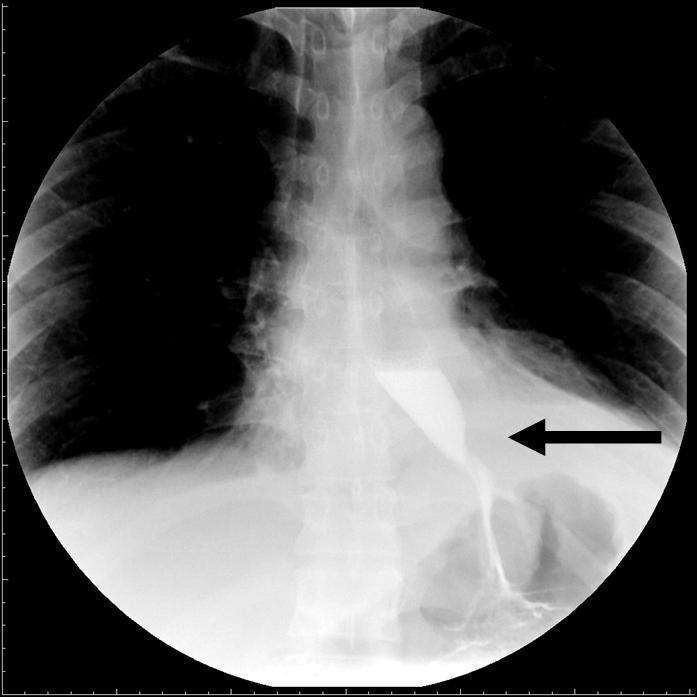

图一 术前上消化道造影图二术后上消化道造影食管裂孔疝以食管反流病

图3 术前x线造影提示巨大食管裂孔疝 术后消化道造影见